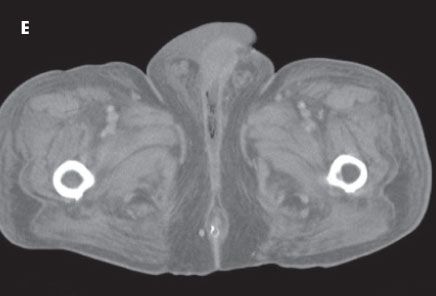

The follow-up CT scans of the abdomen and pelvis depicted dramatic improvement (E). The extraluminal gas had nearly resolved. The patient’s clinical course was ultimately favorable, and he was discharged.